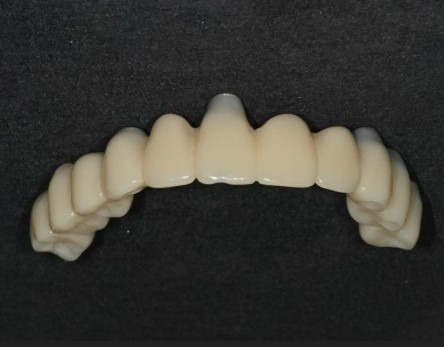

디지털 방식으로 제작된 임시치아

디지털 임시치아는

컴퓨터(CAD) 상에서 디자인하고

3D 프린터, 밀링 머신(CAM)으로 가공하기 때문에

손으로 빚어서 만드는 임시치아보다

훨씬 단단하고 심미적이며,

임시치아라고 해도 3개월,

길게는 1년 이상까지도 사용하면서

임플란트 치아에 적응하는 시간도 가질 수 있습니다.